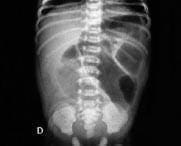

A pesar del tratamiento instaurado tiene deterioro hemodinámico y respiratorio, requiere ventilación mecánica, transfusión de glóbulos rojos, inotrópicos y cambio de antibióticos, además se observa distensión y dolor abdominal; la radiografía de abdomen es compatible con enterocolitis necrotizante (Foto 7), se realiza ileostomía por perforación ileal, continúa antibióticos y apoyo nutricional parenteral, se extuba nuevamente con adecuada tolerancia, se reinicia la vía oral y su evolución es satisfactoria.

Foto 7. Radiografía de abdomen.